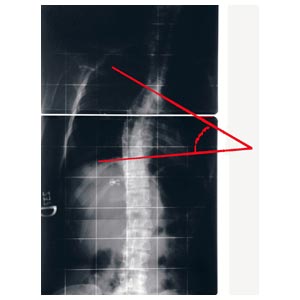

L'angolo di Cobb è dato dalla somma dei due angoli di inclinazione delle limitanti. La misurazione dell'angolo è più veloce del metodo tradizionale (è sufficiente accostare lo strumento alle vertebre limite e leggere il valore sulla scala graduata), non richiede strumenti aggiuntivi, non deteriora le radiografie, semplifica la misurazione eliminando quindi alcune possibili cause di errore.